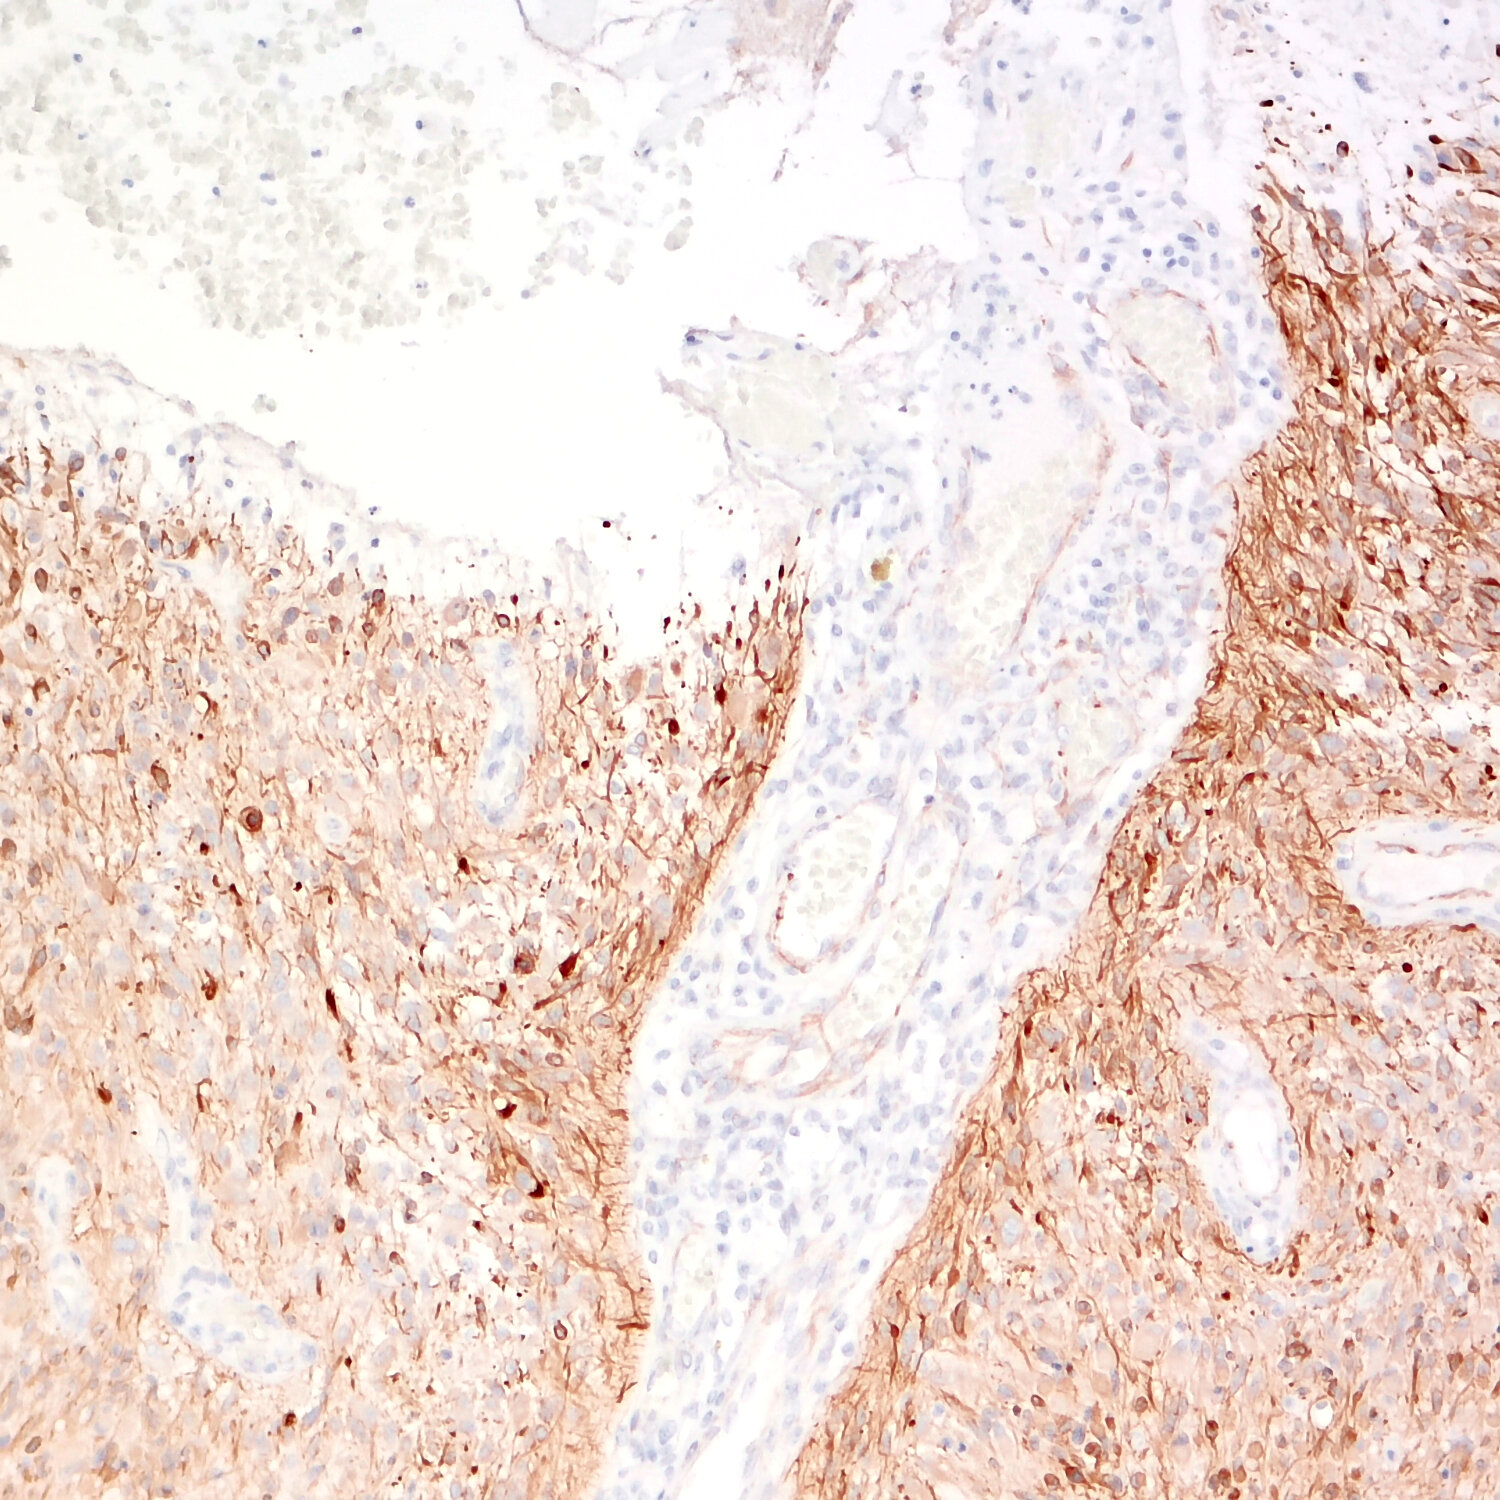

IHC-P: 1 : 500 up to 1 : 2000 gallery

Immunohistochemistry (IHC-P) of formalin fixed, paraffin embedded (FFPE) tissue (some antibodies require special antigen retrieval steps, please refer to the ”Remarks” section). Immunoreactivity is usually revealed by fluorescence or a chromogenic substrate.